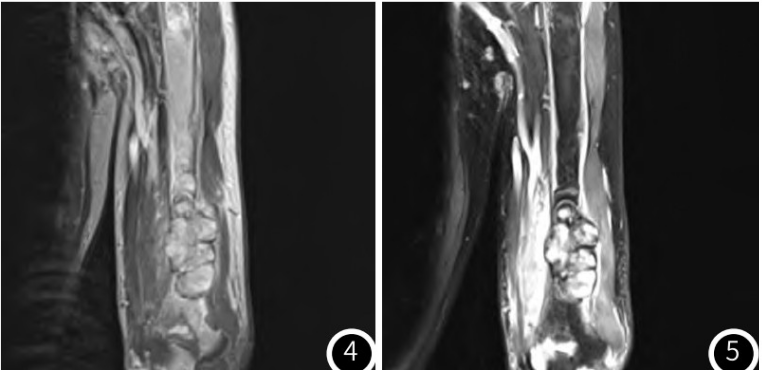

1737674147767571.png

图3-图5左肱骨骨质破坏并T1WI等信号肿物,增强扫描呈不均匀明显强化;T2压脂序列呈不均匀高信号为主,多囊状改变,周围软组织水肿。

MRI表现为多囊样肿物,T1等信号,T2压脂序列呈不均匀高信号为主,增强扫描不均匀明显强化,周围软组织水肿,与钱占华等人的总结一致。PET-CT表现为高代谢肿物。甲状旁腺表现为:腺体增大,CT增强明显强化;超声提示丰富血流信号;甲状旁腺显像阳性。